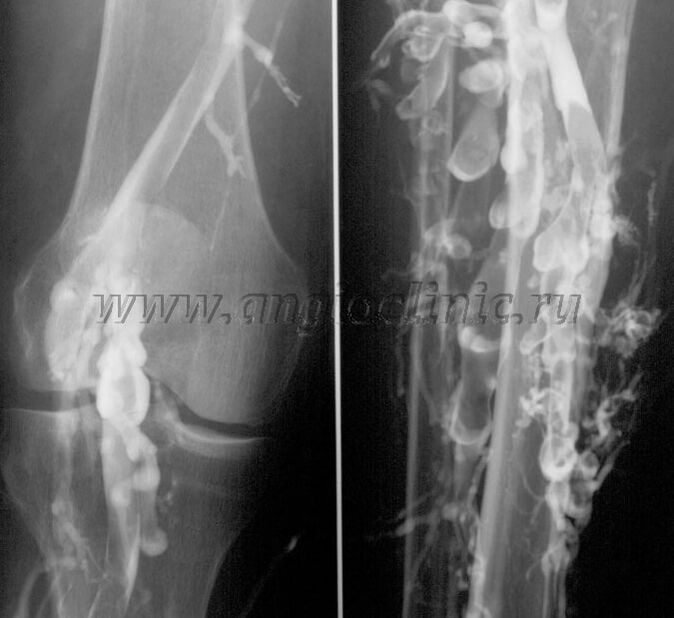

Contrast venography

Usually, an ultrasound scan is sufficient for a complete diagnosis of venous pathology, but in some cases it is necessary to examine the relationship between the state of the deep and superficial venous systems, especially in the case of recurrent varicose veins and secondary varicose veins.

Contrast X-ray examination is used to solve these problems.The saphenous veins are punctured and contrast is administered.The movement of the contrast is observed on the monitor of the X-ray machine and all necessary examinations and projections are performed.Currently, venography for varicose veins is used very rarely.